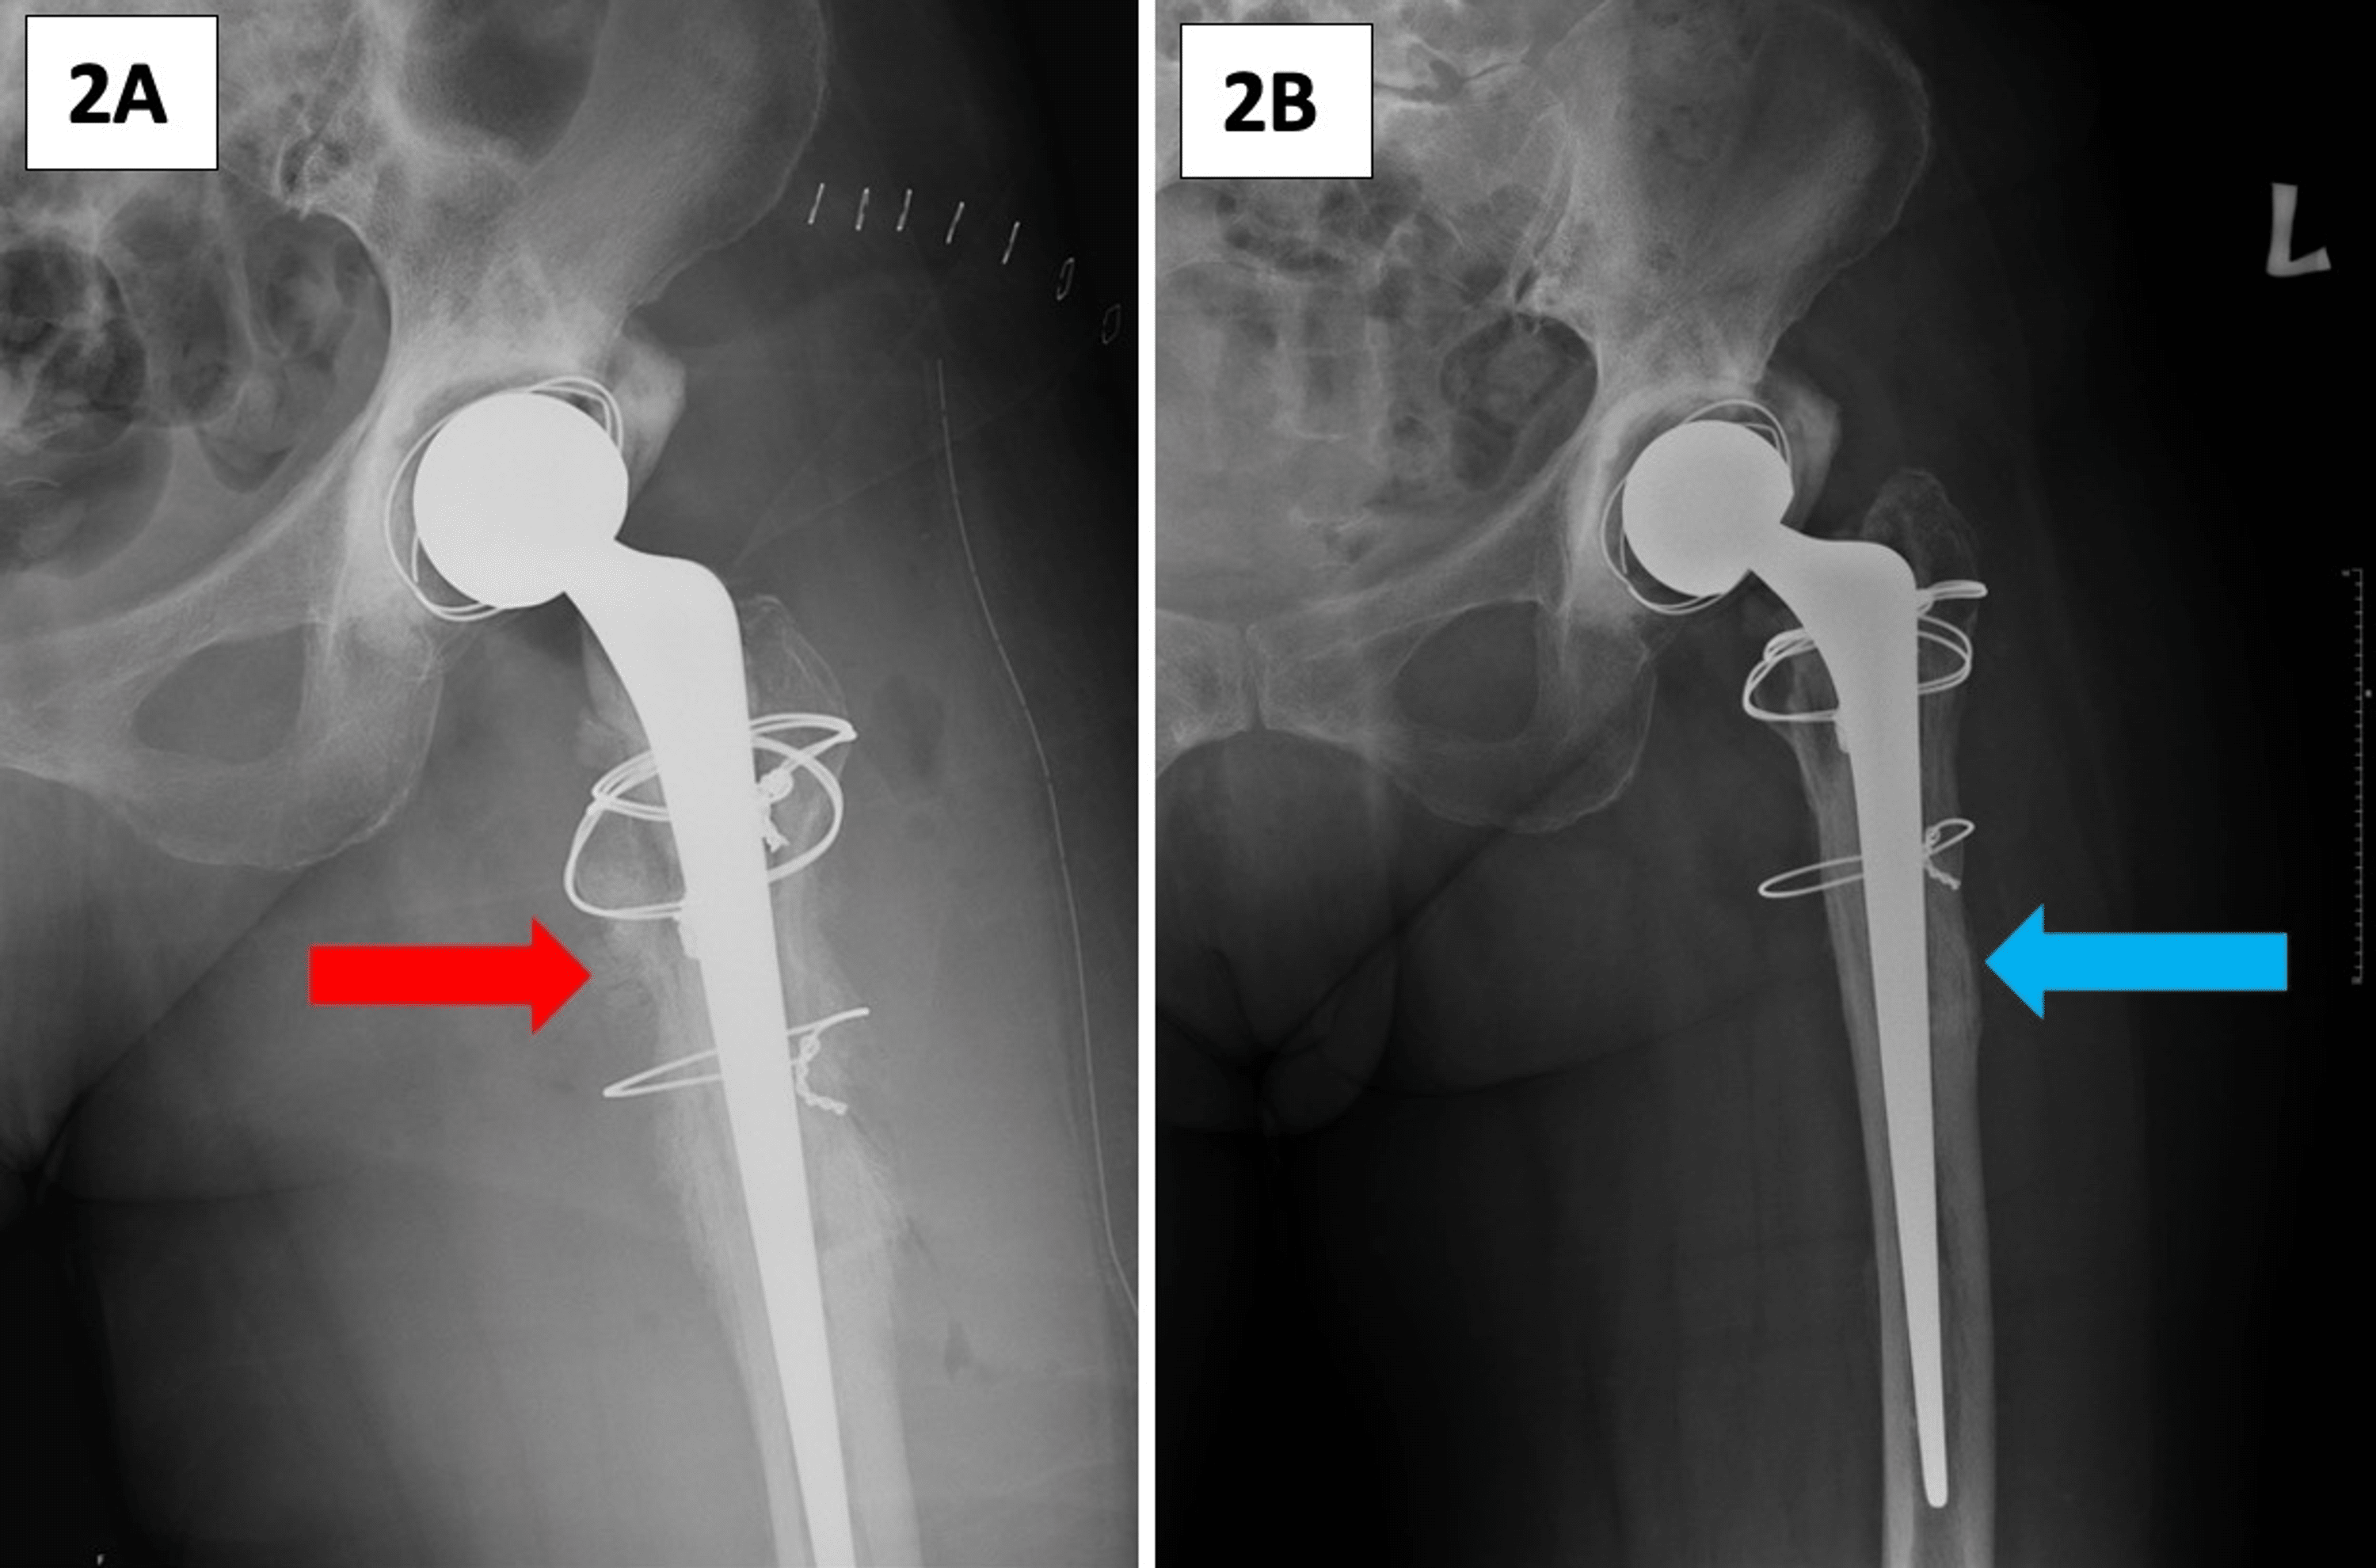

Anteroposterior radiographs of the hip spacer A) without cementation How Much Weight Can You Put On A Hip Spacer the use of spacers provides a lot of advantages like maintaining limb length, joint mobility, and partial weight. learn how to rehabilitate patients with hip spacer implants after infection or fracture of the hip joint. learn about revision surgery for hip replacement, which is needed when the original implant fails due to loosening, infection, dislocation, or fracture. How Much Weight Can You Put On A Hip Spacer.